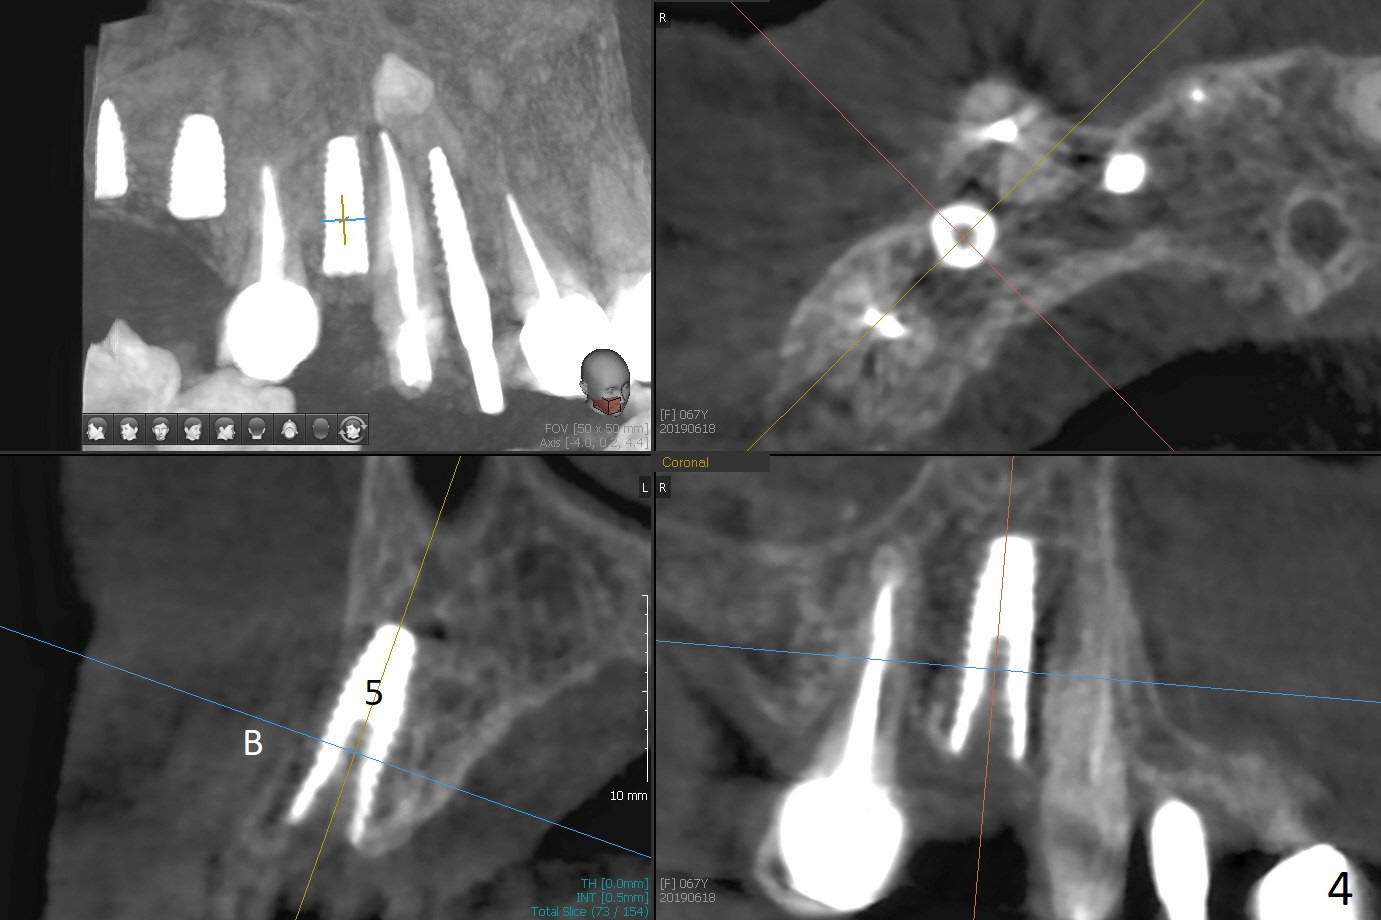

Two of 5x8.5 mm implants are placed at #2 and 3 with sinus lift using water ballooning technique; to avoid invading the neighboring root tips, an intraop PA is taken with a 2.2x11.5 mm drill at #5 (Fig.1). When a 2.5x11.5 mm 1-piece implant is placed at #7, there is 2.4 mm clearance from the impacted tooth (Fig.2). Following 1 mm deeper placement of the 1-piece implant, CT is taken to make sure that the threads are completely covered palatally (Fig.5 P). Interesting is that the sinus membrane is thickened at #2 and 3 (Fig.3 M), as compared to the clear sinus before surgery (Fig.3'). Bone graft is limited in the sinus (Fig.3 arrowheads). The implant at #5 (3.5x11.5 mm) is precisely placed subcrest bucco(B)-palatally (Fig.4). Since the limited field viewed CT does not cover the implant at #2 (Fig.3), immediate postop PA is taken (Fig.6). In fact all of the implants are placed subcrestal, as shown by intraoral X-ray 4 months postop (Fig.7-9). The abutments at #2, 3 and 5 are retorqued (30 Ncm) after crowns' try in and adjustment (Fig.10,11). There is a vertical gap between the implant and abutment at #2 (Fig.11 ^) and a horizontal one at #5 (<). There is apparently no bone loss 1 year 5 months post cementation (Fig.12).